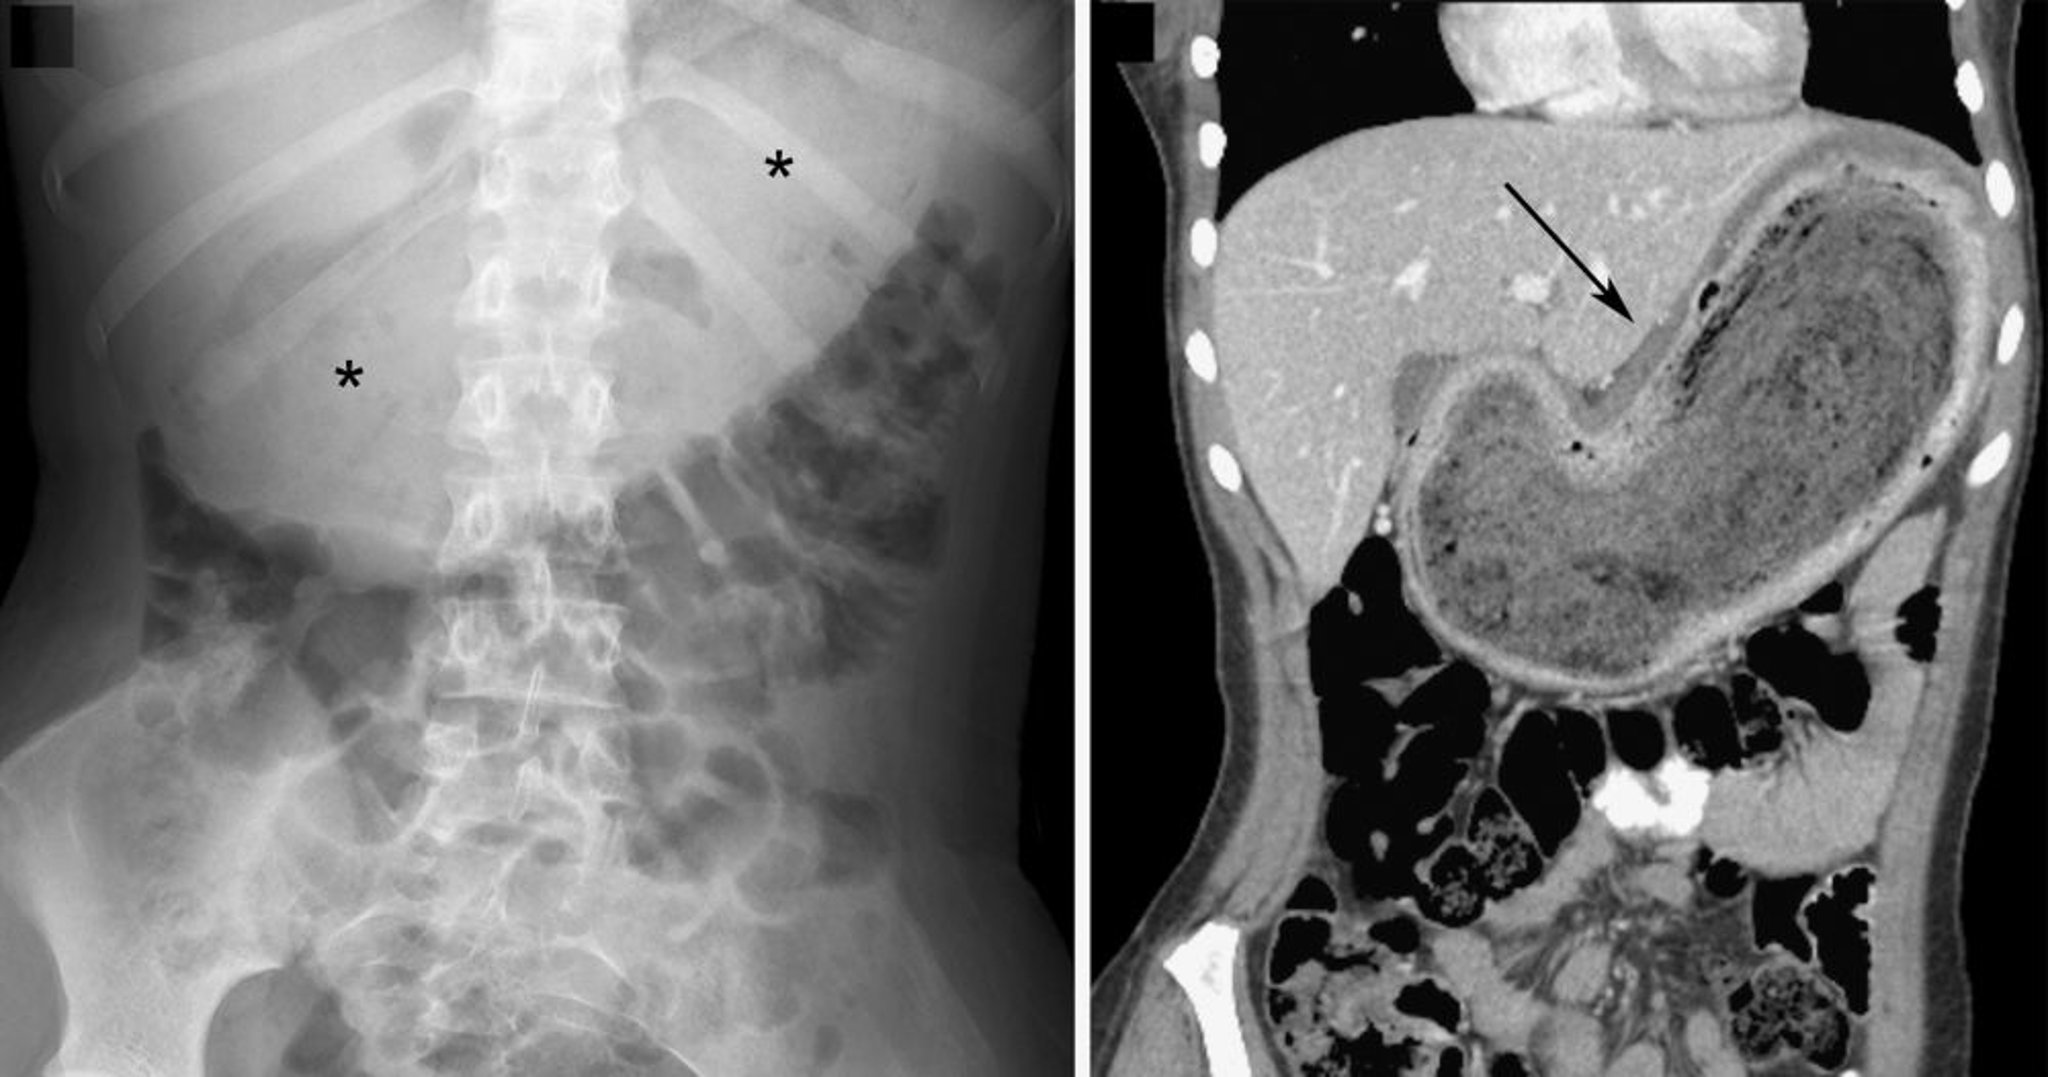

Bezoar (Befunde der bildgebenden Untersuchung)

Im Röntgenbild links wird der Bezoar durch eine große Weichteilmasse in der Mittellinie des oberen Abdomens mit einem gesprenkelten Muster von intraläsionalem Gas (Sternchen) angezeigt. In der koronalen CT-Aufnahme rechts ist der Bezoar durch die heterogene Masse (Pfeil) angedeutet. In beiden Bildern ist eine inferiore Verlagerung der Darmschlingen zu sehen.